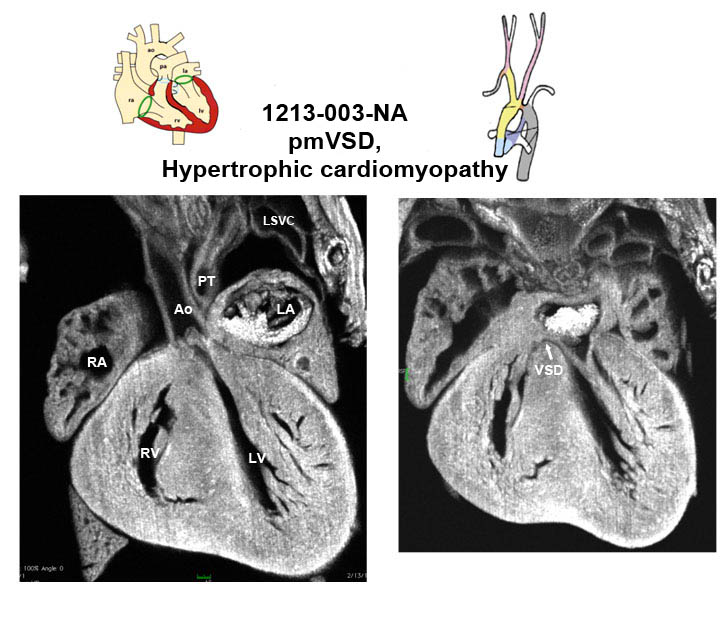

Caption EFIC summary

Copyright This image is from the Laboratory of Dr. Cecilia Lo, a member of the Cardiovascular Development Consortium (CvDC), Bench to Bassinet (B2B) program of the National Heart Lung and Blood Institute (NHLBI), and is displayed with the permission of the authors. J:175213

Rfx3b2b1213Clo regulatory factor X, 3 (influences HLA class II expression); Bench to Bassinet Program (B2B/CVDC), mutation 1213 Cecilia Lo

Rfx3b2b1213Clo/Rfx3b2b1213Clo C57BL/6J-Rfx3b2b1213Clo